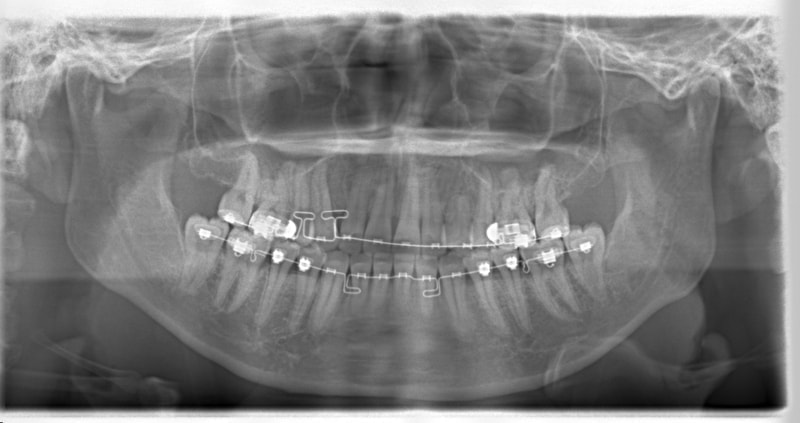

左上3番埋伏歯

治療法:フルパッシブブラケット:T21

治療開始から24ヶ月後